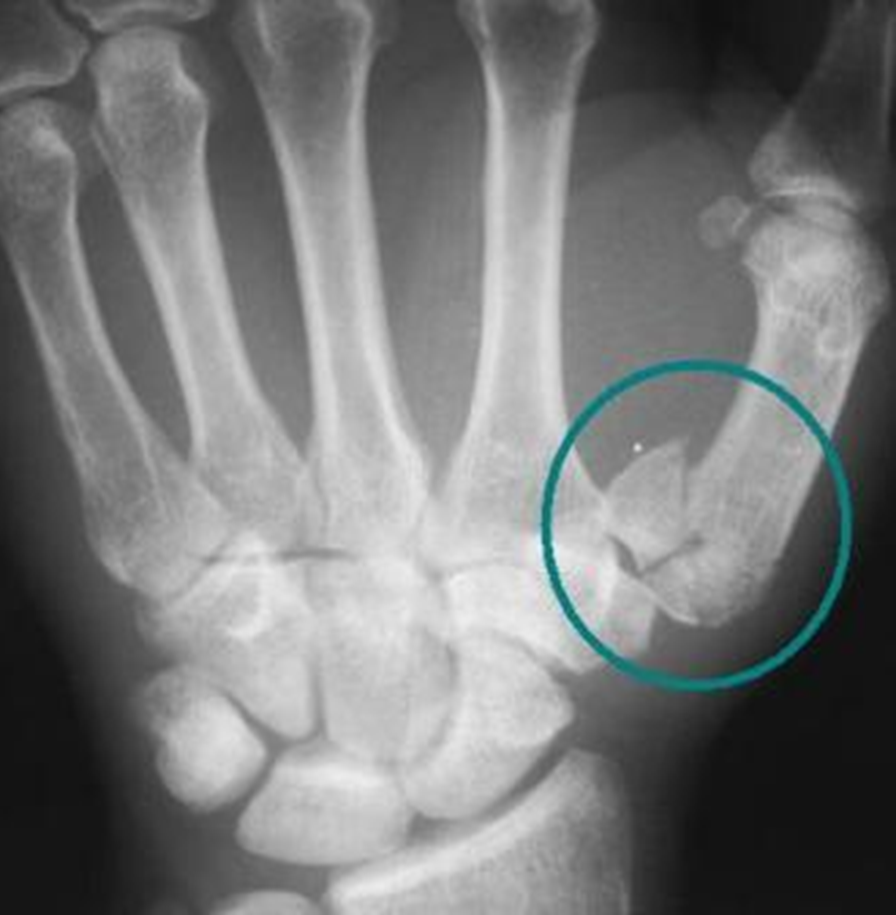

What does this image show

gap between the scaphoid and lunate